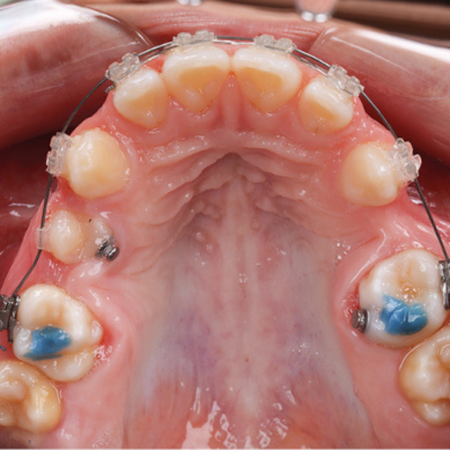

INTRODUÇÃO: O gerenciamento dos espaços das agenesias dentárias é frequentemente relatado como um desafio adicional para o tratamento ortodôntico e, quando associado à má oclusão esquelética, torna o tratamento mais complexo. OBJETIVO: Neste relato de caso, objetivou-se apresentar um tratamento ortopédico seguido de tratamento ortodôntico compensatório de um paciente Classe III esquelética severa com agenesia dentária múltipla. RELATO DE CASO: Paciente do sexo masculino, com 14 anos de idade, teve um plano de tratamento atípico, inicialmente tratado com máscara facial...

INTRODUÇÃO: O gerenciamento dos espaços das agenesias dentárias é frequentemente relatado como um desafio adicional para o tratamento ortodôntico e, quando associado à má oclusão esquelética, torna o tratamento mais complexo. OBJETIVO: Neste relato de caso, objetivou-se apresentar um tratamento ortopédico seguido de tratamento ortodôntico compensatório de um paciente Classe III esquelética severa com agenesia dentária múltipla. RELATO DE CASO: Paciente do sexo masculino, com...

INTRODUCTION: Space management of tooth agenesis is often reported as an additional challenge for orthodontic treatment and, when associated with skeletal malocclusion, makes the treatment more complex. OBJECTIVE: The objective of this case report was to present an orthopedic treatment followed by comprehensive orthodontic treatment of a severe skeletal Class III patient with multiple tooth agenesis. CASE REPORT: A 14-year-old male had an atypical treatment plan, starting with facemask...